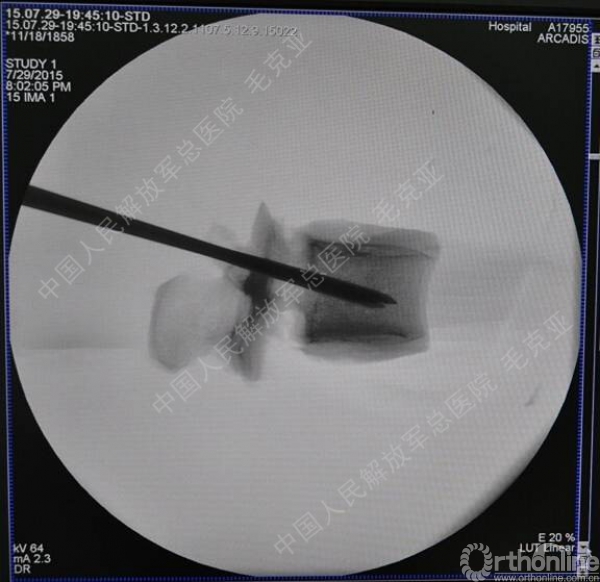

导语:随着社会老龄化的不断加速,骨质疏松性椎体压缩骨折作为一种普遍存在的老年骨科疾病已经成为现今骨科界的一个热点话题。传统的保守疗法治疗效果不佳,而现有的椎体增强技术又具有多种风险和缺陷。针对这种现状,中国人民解放军总医院毛克亚教授提供了一种新的解决方法。